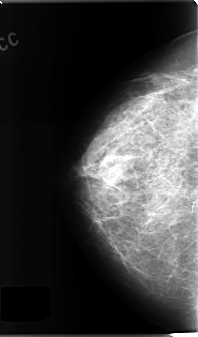

C_0136_1.RIGHT_CC

RIGHT_CC LINES 4712 PIXELS_PER_LINE 2768 BITS_PER_PIXEL 12 RESOLUTION 50 NON_OVERLAY